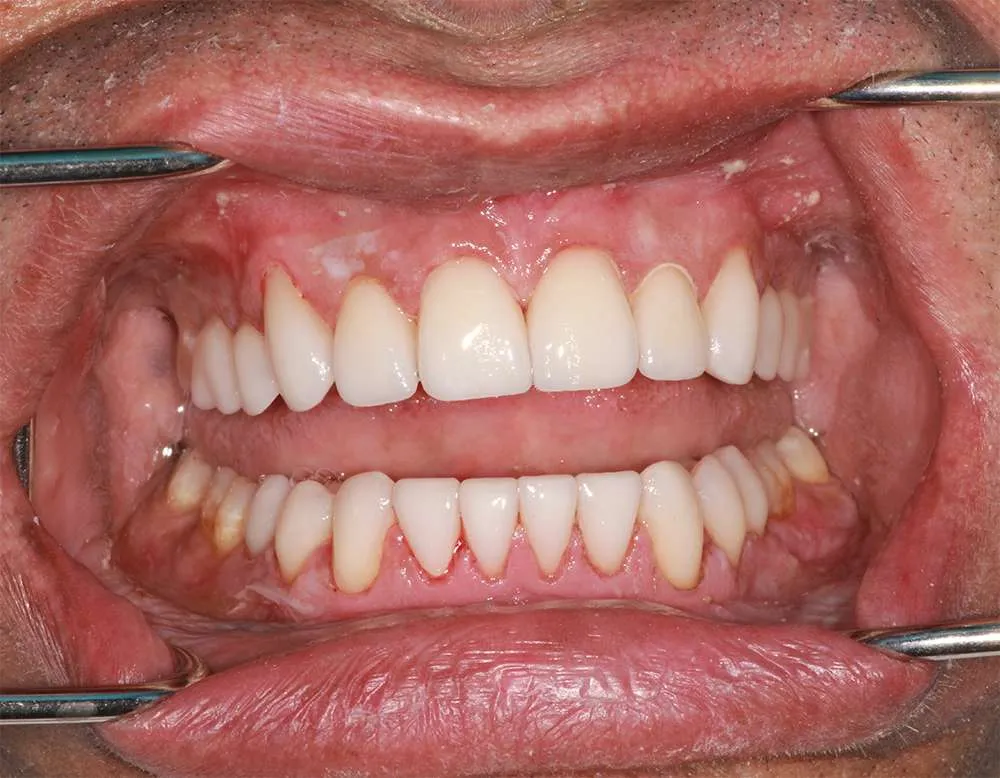

Real Stories, Real Results: Case Studies Showcasing How Our Personalized Approach Transforms Smiles and Lives

Complex Cases

Witness the Remarkable Changes We Can Achieve

Ultra-thin veneers are crafted from high-quality materials that closely resemble the look and feel of natural teeth. The translucency and texture of these veneers mimic the appearance of real enamel, ensuring that your smile looks natural and aesthetically pleasing. Each veneer is custom-made to match the color, shape, and size of your existing teeth, blending seamlessly with your natural smile. This attention to detail ensures that your veneers are virtually indistinguishable from your natural teeth, providing you with a flawless, beautiful smile.